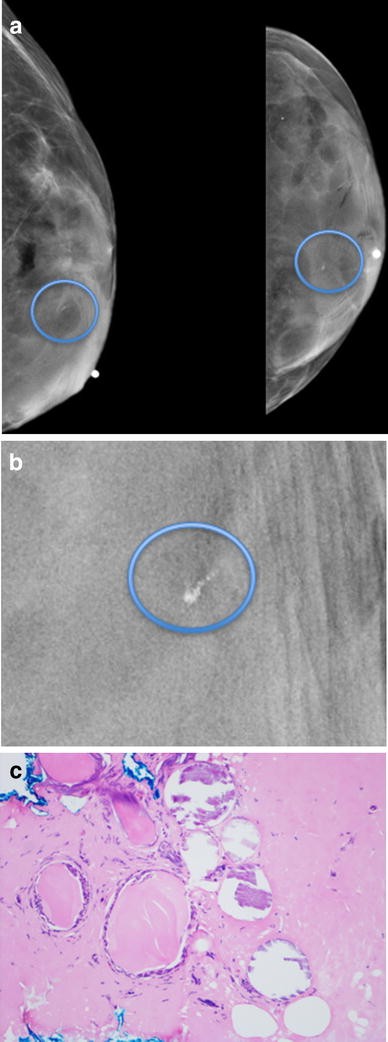

La mastografía es una herramienta de detección temprana del cáncer de mama que se utiliza ampliamente en todo el mundo. En general, se recomienda que las mujeres se realicen una mastografía cada dos años a partir de los 50 años. Sin embargo, hay algunos factores de riesgo que pueden aumentar la necesidad de realizar una mastografía con mayor frecuencia.